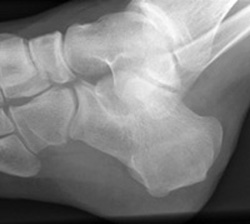

Lateral views of calcaneal fractures

Lateral view